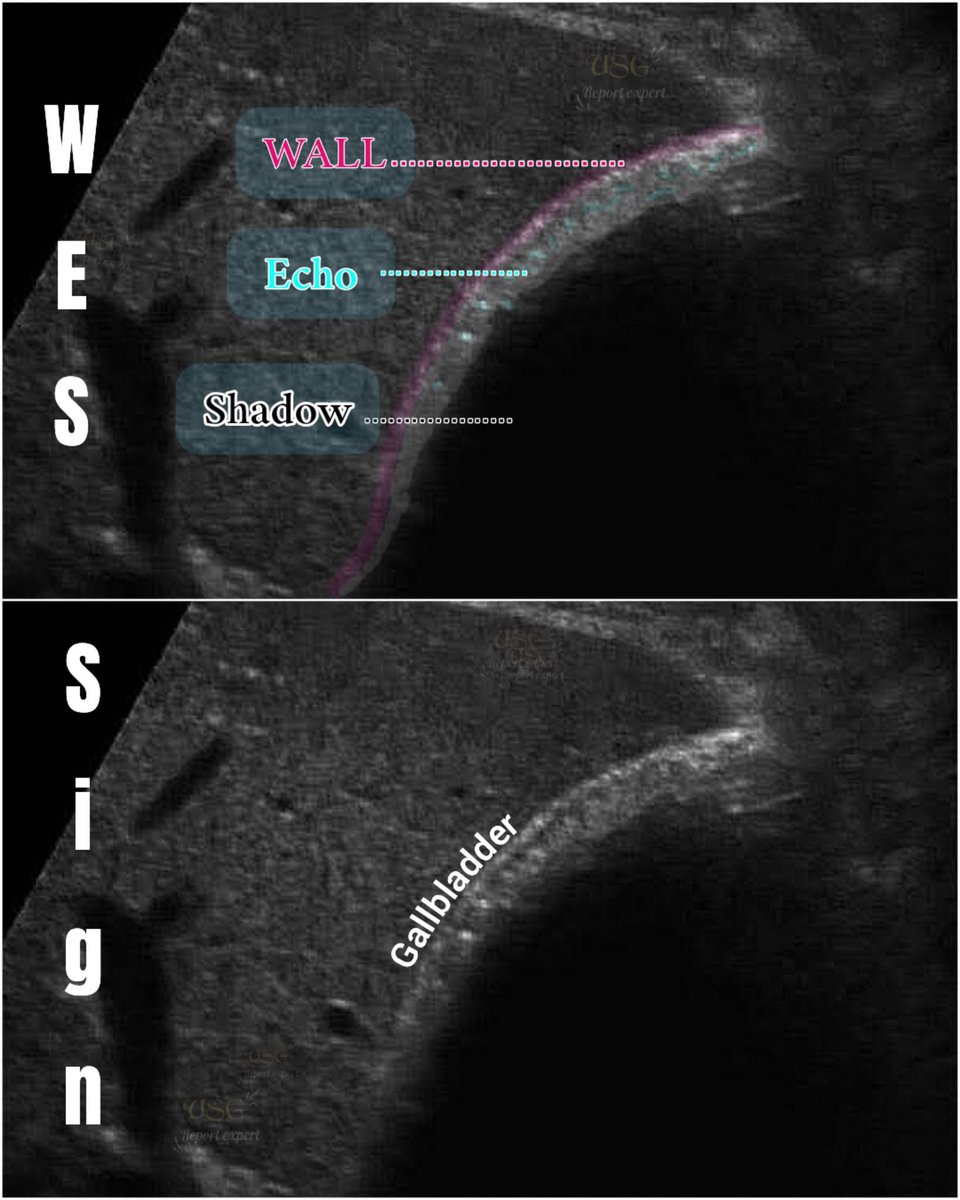

This 50 years female pt came with acute pain in the epigastrium and jaundice. Your opinion? Name of the sonographic sign?? Area of scan :RUQ. #EchoTech

This 50 years female pt came with acute pain in the epigastrium and jaundice. Your opinion? Name of the sonographic sign?? Area of scan :RUQ. #EchoTech